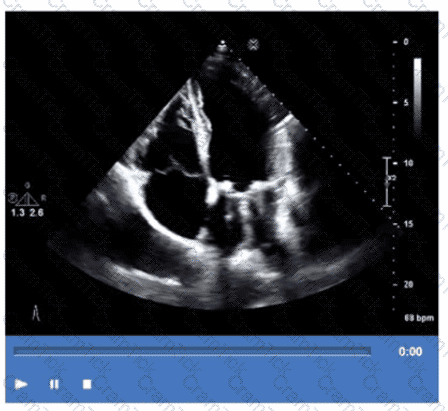

Which step is next in further evaluation of the abnormality shown in this video?